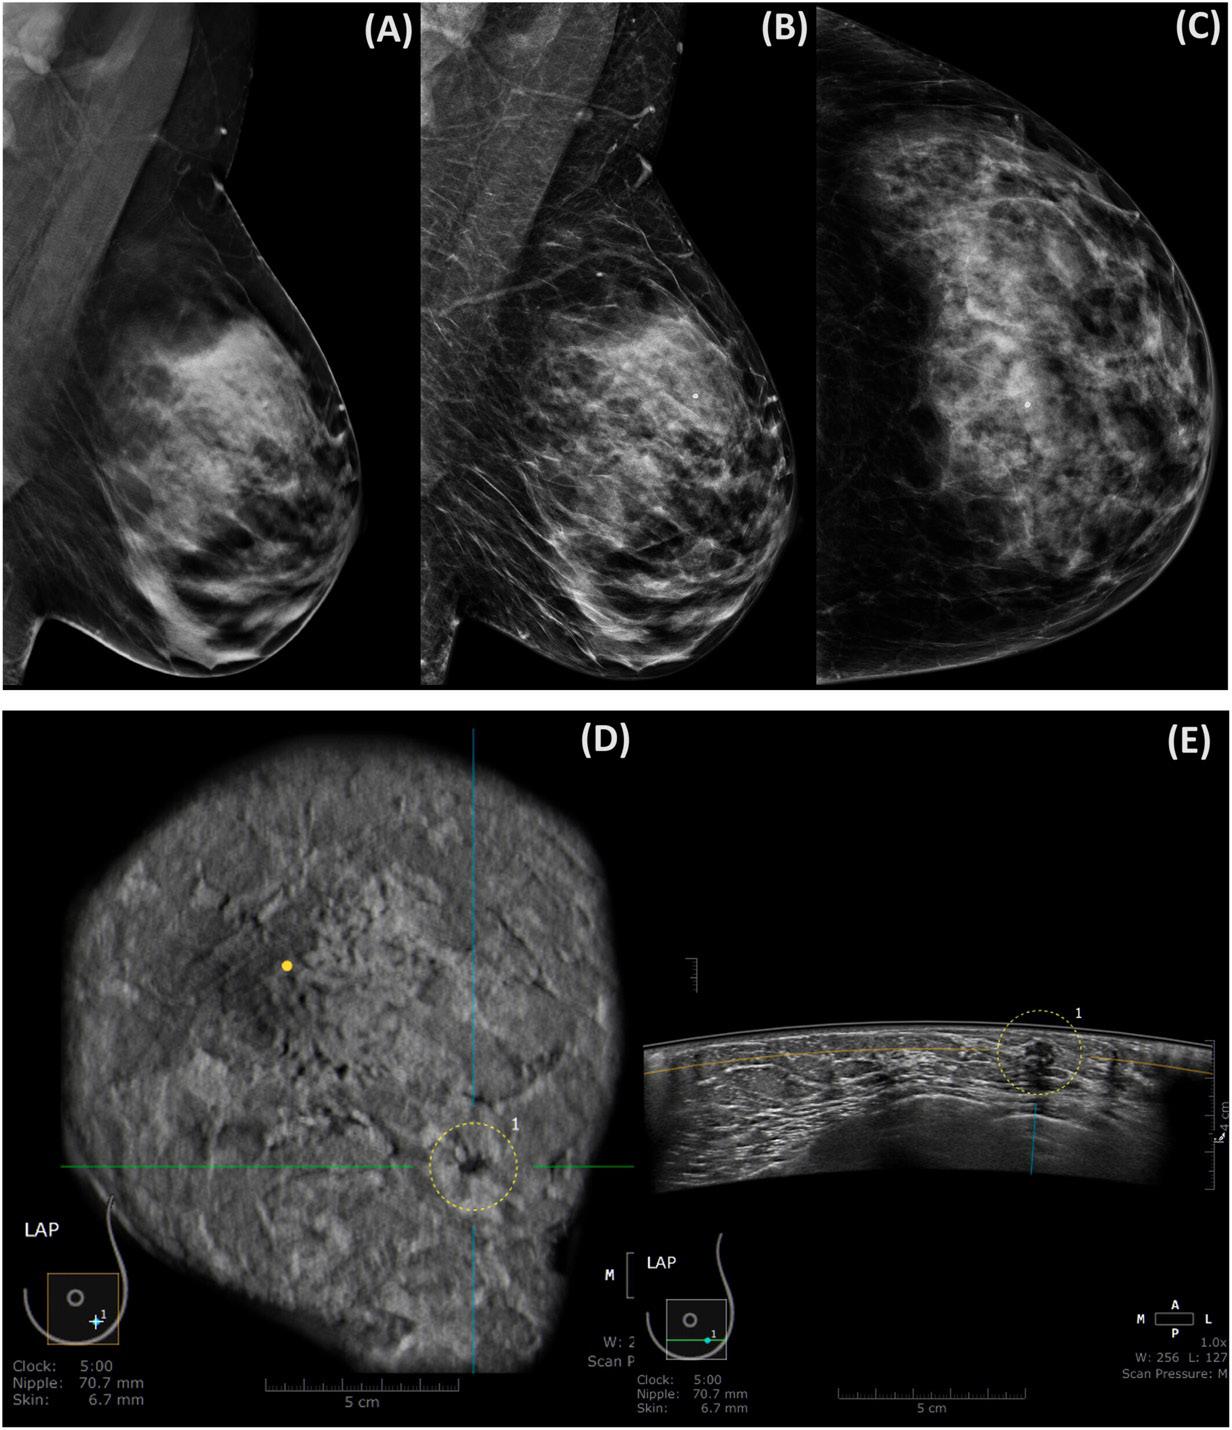

4. ABUS identified 12.5% more invasive cancers than DBT, suggesting it may detect more clinically important tumours (example imaging below)

Figure 1. 50-year-old woman with BI-RAD C-type breast tissue. (A) LMLO DBT slice capturing a potential section of the MLO, providing insight into the location where the mass might be present. (B, C) 2D mammogram of the left breast. (B) 2D synthetic LMLO view. (C) 2D LCC view. No evidence of breast cancer is (A, B and C). (D) Coronal ABUS image. (E) Transverse ABUS image. A spiculated irregular mass with a hypoechoic pattern at 5:00 is seen. Histopathology of the lesion showed invasive cancer. Int J Cancer. 2024; 155(8) pg 1470